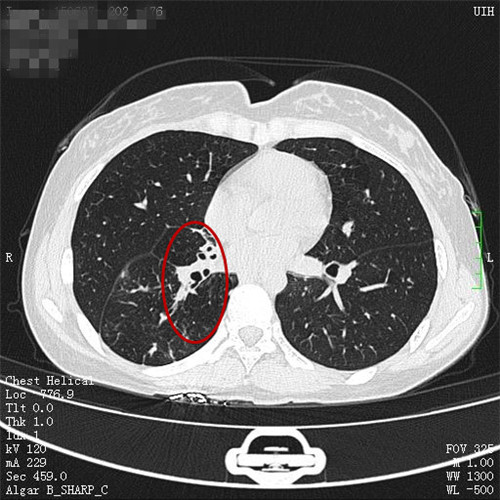

治疗前和治疗后

谭建龙副主任医师在接诊后通过详细的病史询问和体格检查,认为王女士很可能有肺结核合并气管支气管结核,立即进一步安排胸部CT检查和支气管镜检查,胸部CT检查发现其的右侧中间段支气管闭塞,右肺有2/3的肺被完全阻塞,支气管镜检查也发现右中间段支气管被大量的坏死物堵塞,多处气管都被病变累及,若不积极治疗,病变可能累及双肺,给病人造成不可挽救的伤害。

在呼吸科二病区接受了规律的全身抗结核治疗以及支气管镜下等介入冷冻治疗、药物灌注治疗后,王女士的气管、支气管病变得到控制,闭塞的右肺也得以恢复,咳嗽和呼吸困难症状也完全缓解。11月9日,王女士出院了,她心有余悸地说,没想到咳嗽居然是这么严重的疾病,应该早一点来医院的。